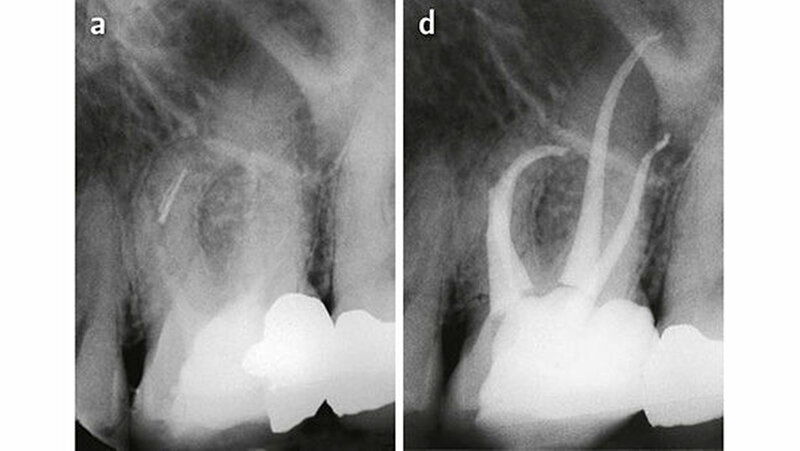

Anschließend kann es mittels Ultraschallspitzen oder feinster Trepanbohrer umfahren und allenfalls gelockert werden (Ward et al. 2003) (Abb.1). Falls das Instrument trotz Ultraschallvibration nicht aus dem Kanal hinausbefördert wird, bietet sich die Möglichkeit, es in einer Hohlnadel zu verkeilen oder zu verkleben und herauszuziehen (Suter 1998; Schutz-Bongert & Tulus 2016) (Abb. 2). Dabei ist es manchmal schwierig, die zueinander passenden Dimensionen von Hohlnadeln und Hedströmfeilen zum Verkeilen des Fragments zu finden. Alternativ kann das Instrument nach 'Bypassing' (s.o.) oft mittels Ultraschall oder Handinstrumenten aus dem Kanal hinausbefördert werden.